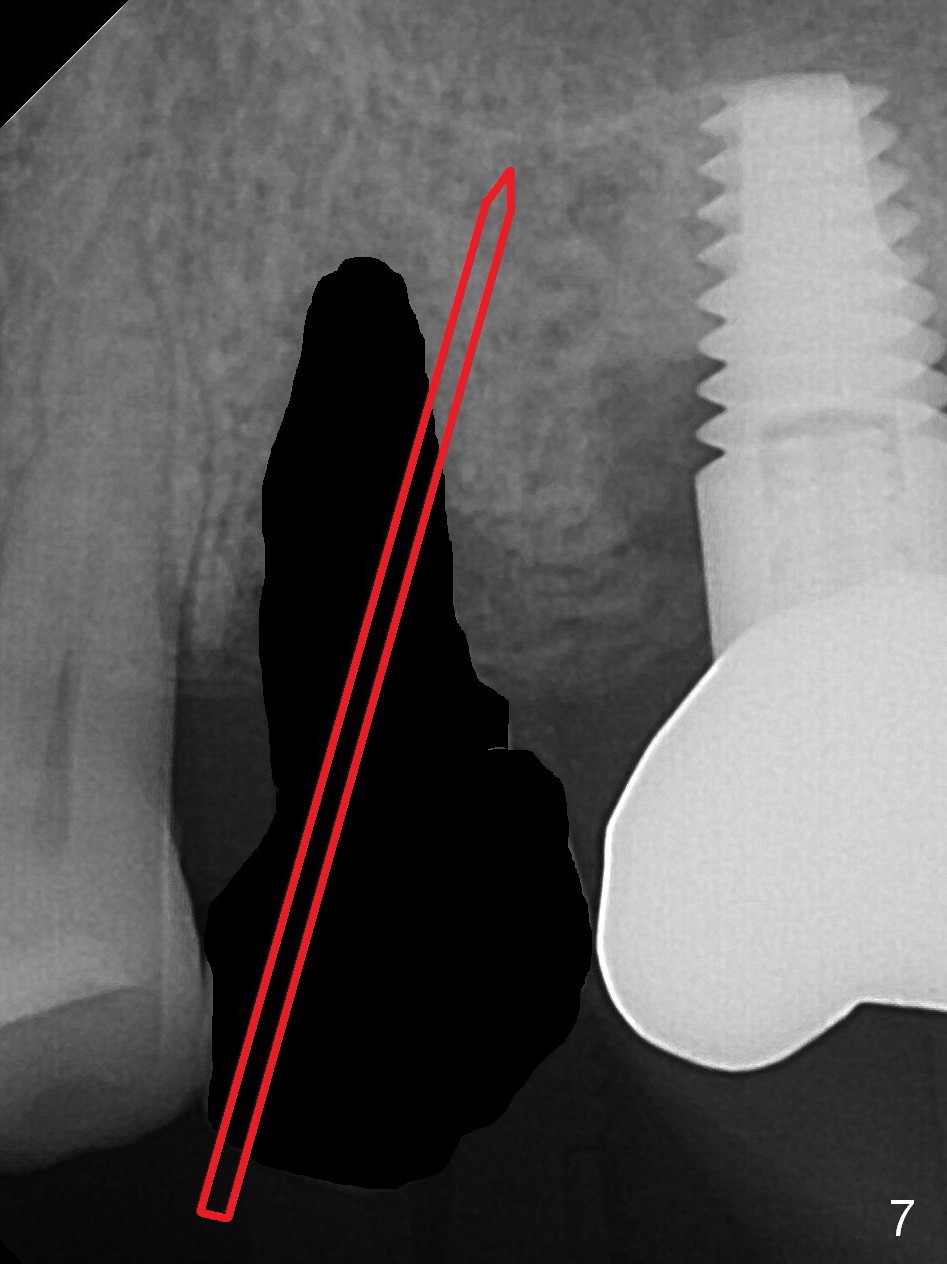

To compensate for bruxism, the implant at #13 should be as large and long as possible.  After extraction (Metronidazole), take PVS impression of the socket.  Start osteotomy in the distal wall of the socket (Fig.7 red).  The initial depth is 11 mm (gingival level).  Increase the depth once the trajectory is confirmed (Fig.9).  After implant placement (Fig.8 green), place bone graft (red circles) in the mesial portion of the socket as well as in the coronal portion of the implant at #14 (incision).  Use a healing abutment (pink), collagen plug (yellow) and suture to close the socket opening.